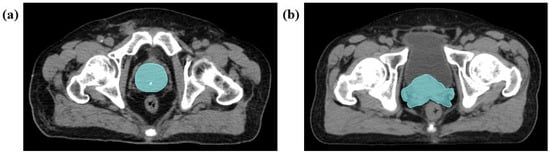

2.4.2. Medical Image Segmentation